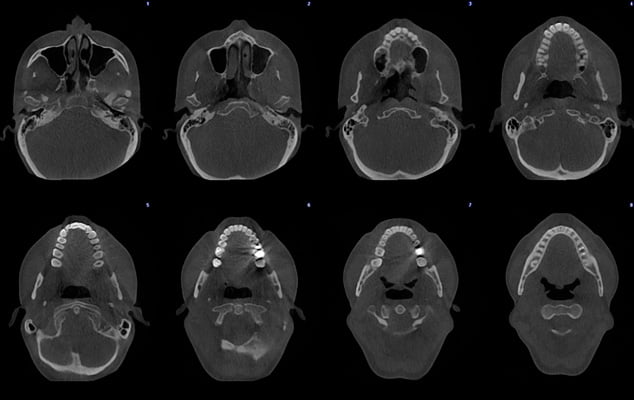

Protokół Planmeca Ultra Low Dose okazał się idealny do szerokiego zakresu zastosowań klinicznych, od ortodoncji do planowania implantów, chirurgii szczękowej oraz badań dróg oddechowych i zatok.

Planmeca Ultra Low Dose może być stosowany ze wszystkimi rozmiarami wokseli i wszystkimi trybami obrazowania, od najmniejszego rozmiaru woksela do największego pola widzenia (FOV). Ten protokół obrazowania jest idealny, gdy wymagane są szczegółowe informacje anatomiczne przy bardzo niskich dawkach promieniowania.

Wysoka rozdzielczość i duża dawka nie zawsze są niezbędnymi standardami i często mniej znaczy więcej. Na przykład obrazowanie ultraniskodawkowe Planmeca jest niezbędne do uwidocznienia kanału nerwu żuchwowego przy planowaniu implantów i ekstrakcji zębów mądrości. Wszystko to można osiągnąć przy wyjątkowo niskich dawkach.